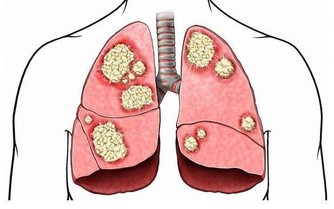

4、多吃黃色蔬菜、紅薯、南瓜、西紅柿和胡蘿蔔等新鮮綠色蔬菜,內含豐富的胡蘿蔔素,

對兒童及成人均有重要的提高免疫力、減少感染、減低腫瘤發病機會的作用。

5、多喝綠茶及多吃深綠色蔬菜、飲料以茶最好,茶以綠茶最佳。

綠茶有明確的抗腫瘤、抗感染作用,品茶能放鬆身心,釋放壓力。

常常喝點綠茶能提神清腦,深綠色蔬菜富含的維生素及礦物質,對人體健康非常有益。